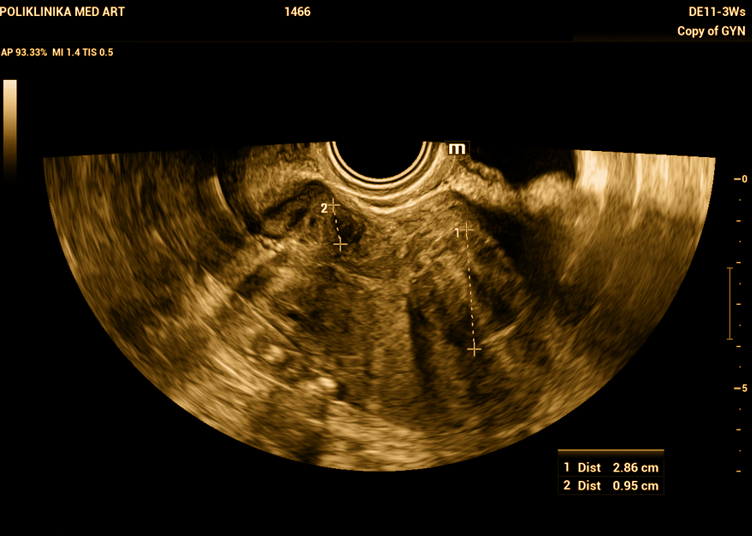

Dva mioma – manji prema području vrata maternice, a veći ulazi u unutrašnjost maternice.

Zbog prodiranja u sluznicu maternice može raditi obilnija i produljena menstrualna krvarenja pa je potrebno odstraniti ga pomoću histeroskopije.